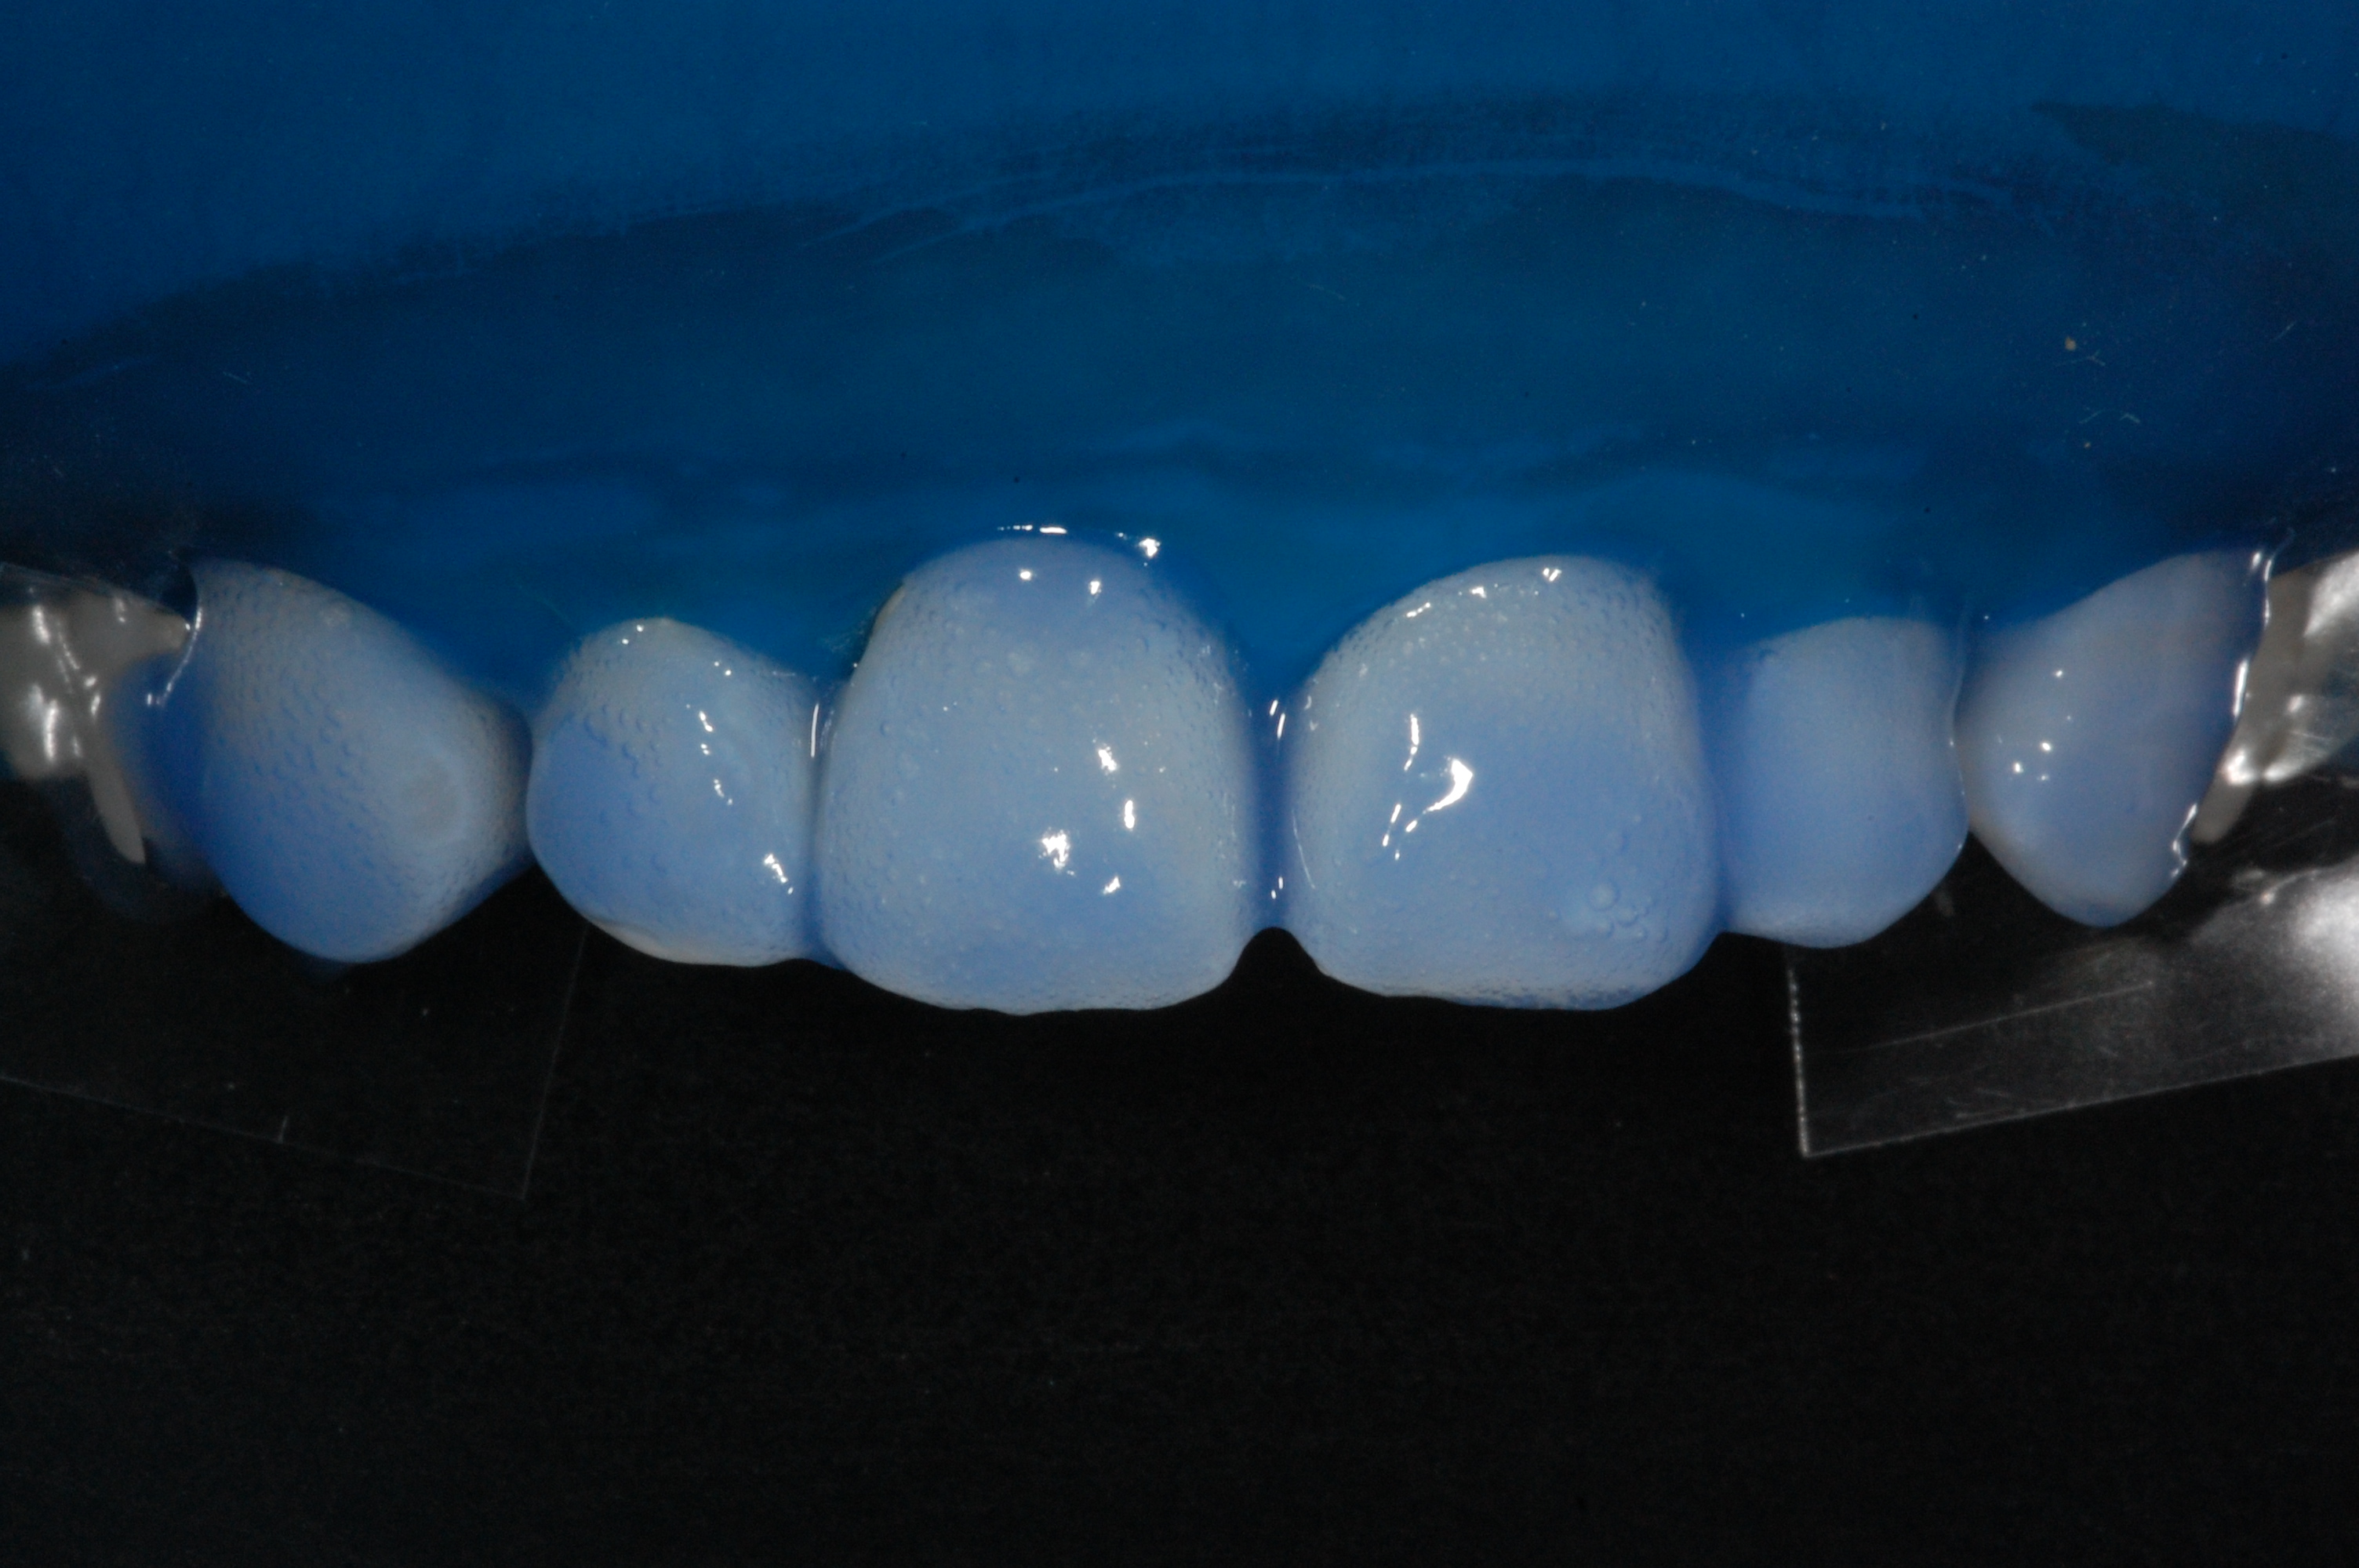

The presence of diastema, between anterior teeth, distorts a pleasing smile by concentrating the observer’s attention on the spaces. The patient’s needs and expectations must be considered in the process of treatment planning to ensure satisfaction with the treatment outcomes. There are many forms of therapy that can be used for diastema closure. A carefully developed diagnosis, which includes a determination of the causal elements and advanced treatment planning, allows the most appropriate treatment to be selected for each case. The aim of this paper is present a multidisciplinary approach as a solution to multiple diastemas in the anterior region using gingival tissue recontouring and direct adhesive restorations, with minimum wear of the dental structure, after the orthodontic intervention discussing the minimal intervention to obtain imperceptive and aesthetic final restoration. Thirty-six months after the treatment was carried out, the final aesthetic was maintained with all dental element details and gingival tissue harmony, without recurrence of periodontal pockets and the preservation of the tooth color and shape.